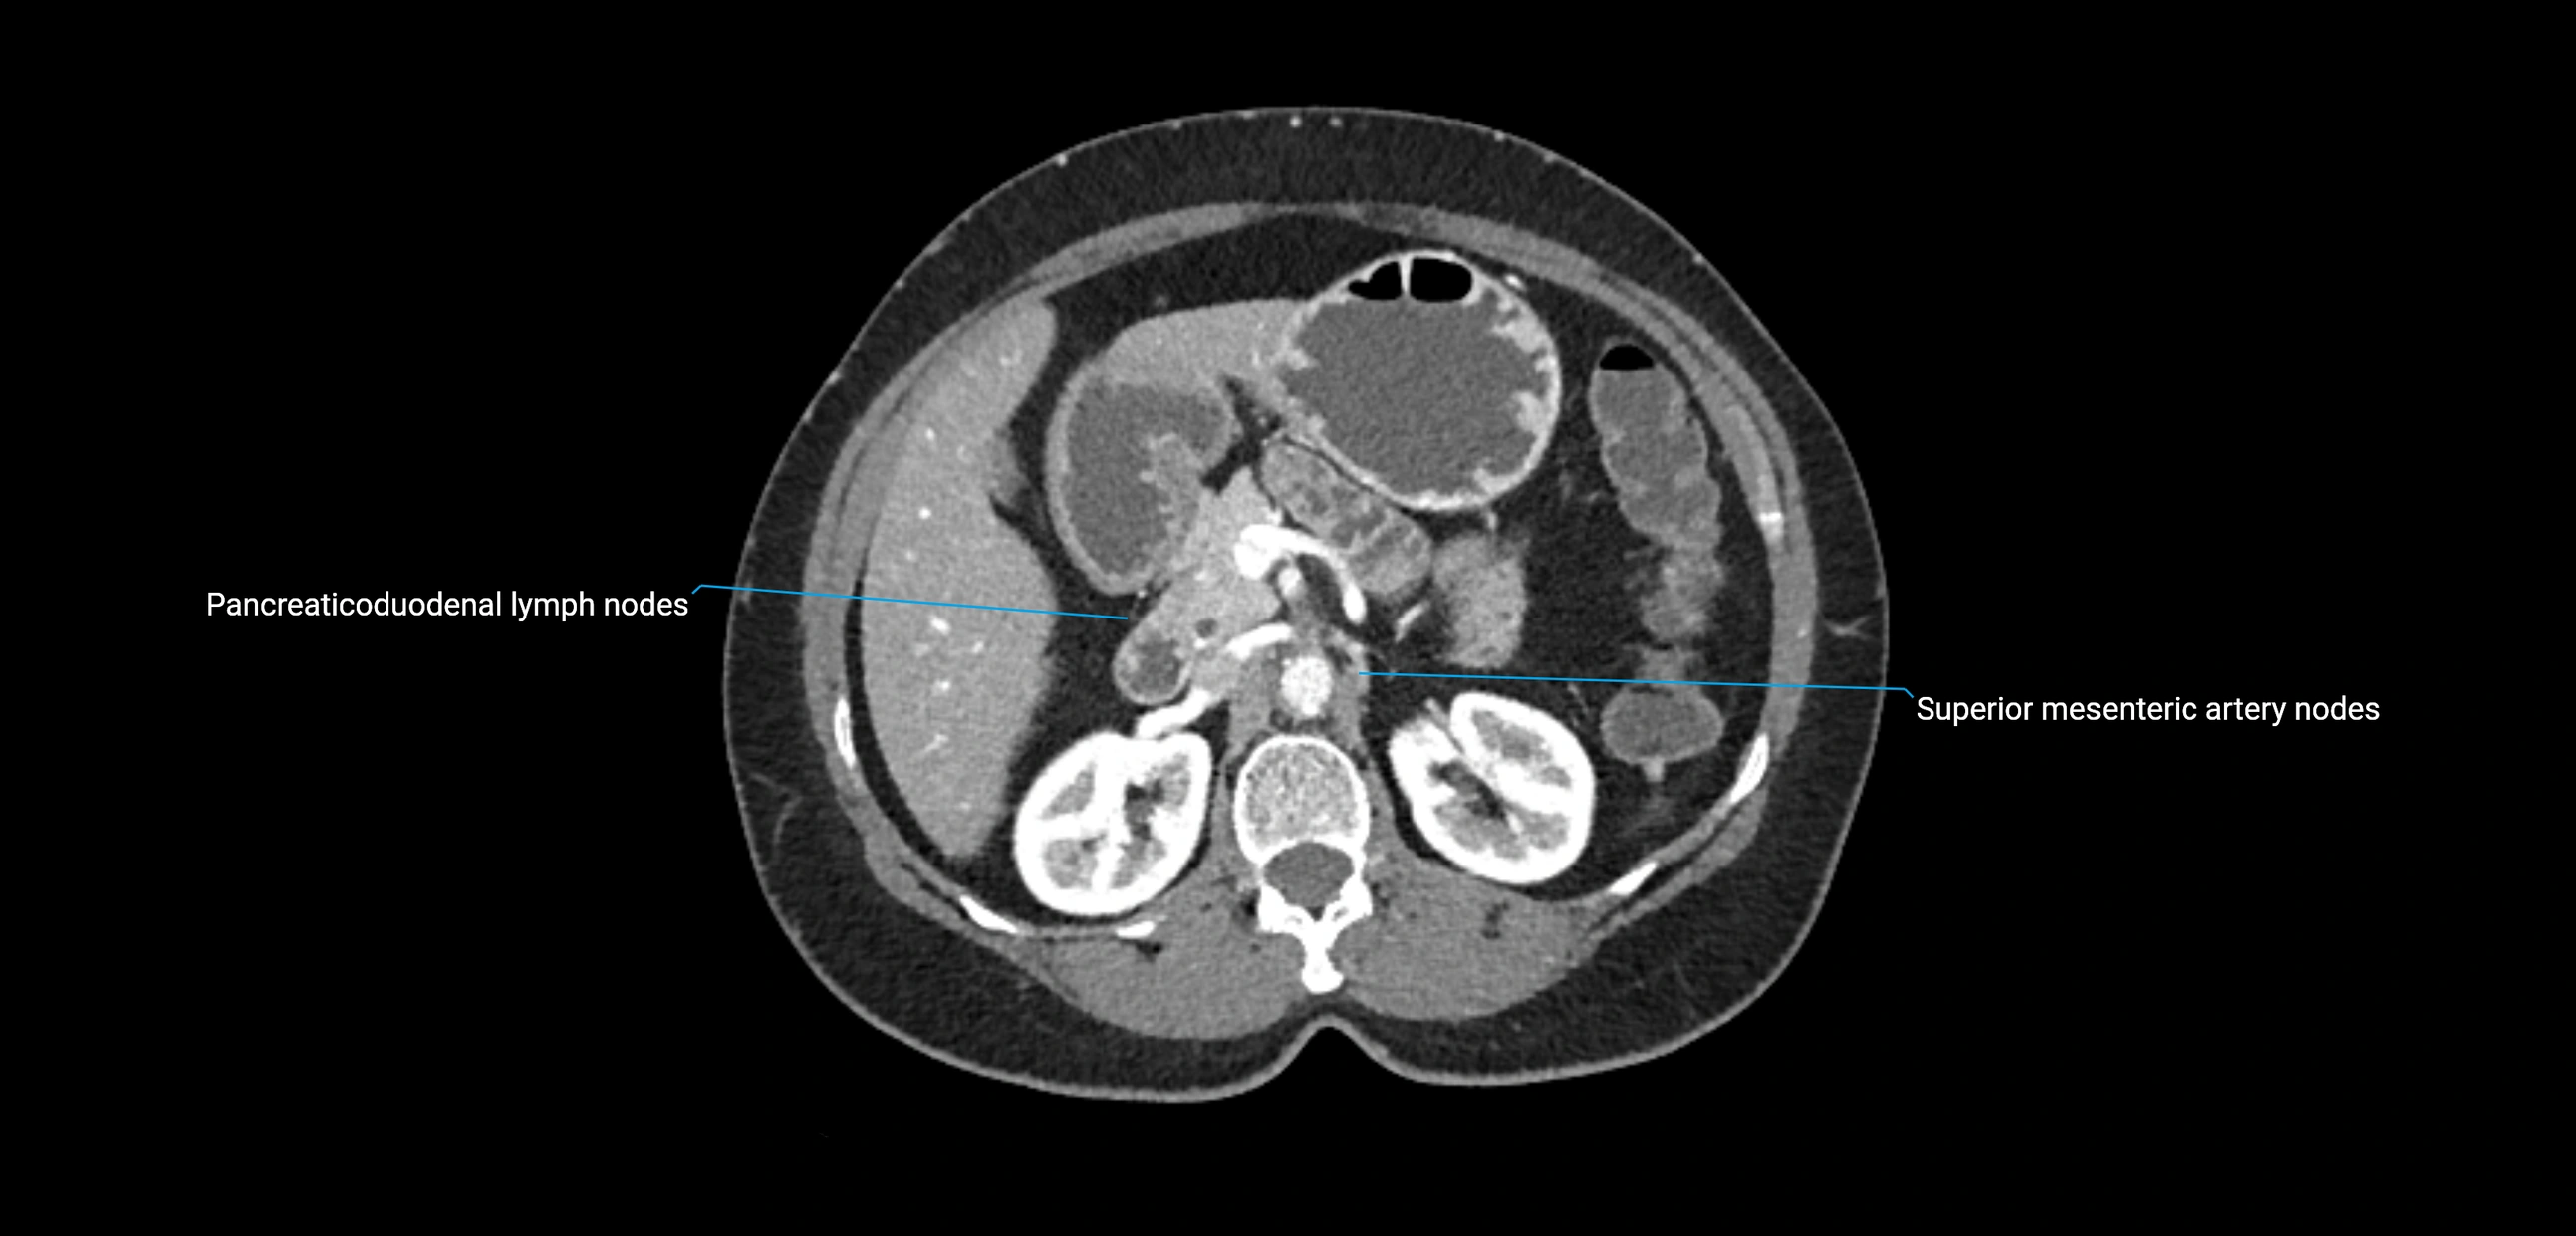

CT Appearance

CT Post-Contrast:

• Normal nodes enhance homogeneously

• Malignant nodes may show heterogeneous enhancement, central necrosis, or conglomerate formation

• Size >1 cm short axis is suspicious, though morphology and distribution are equally important

CT Venography (CTV):

• Demonstrates nodal encasement or compression of adjacent vessels (aorta, IVC, renal veins)

• Useful in staging testicular and ovarian malignancies

• Provides 3D reconstructions for retroperitoneal lymph node dissection planning